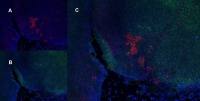

IHC-P analysis of formalin fixed human breast cancer tissue section using GTX32375 CDK5 (phospho Tyr15) antibody.

Antigen retrieval : Heat mediated antigen retrieval with sodium citrate buffer (pH 6.0)